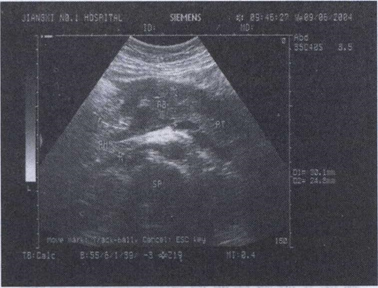

40.男,37岁,健康体检,偶感上腹不适。声像图如图所示,诊断为()